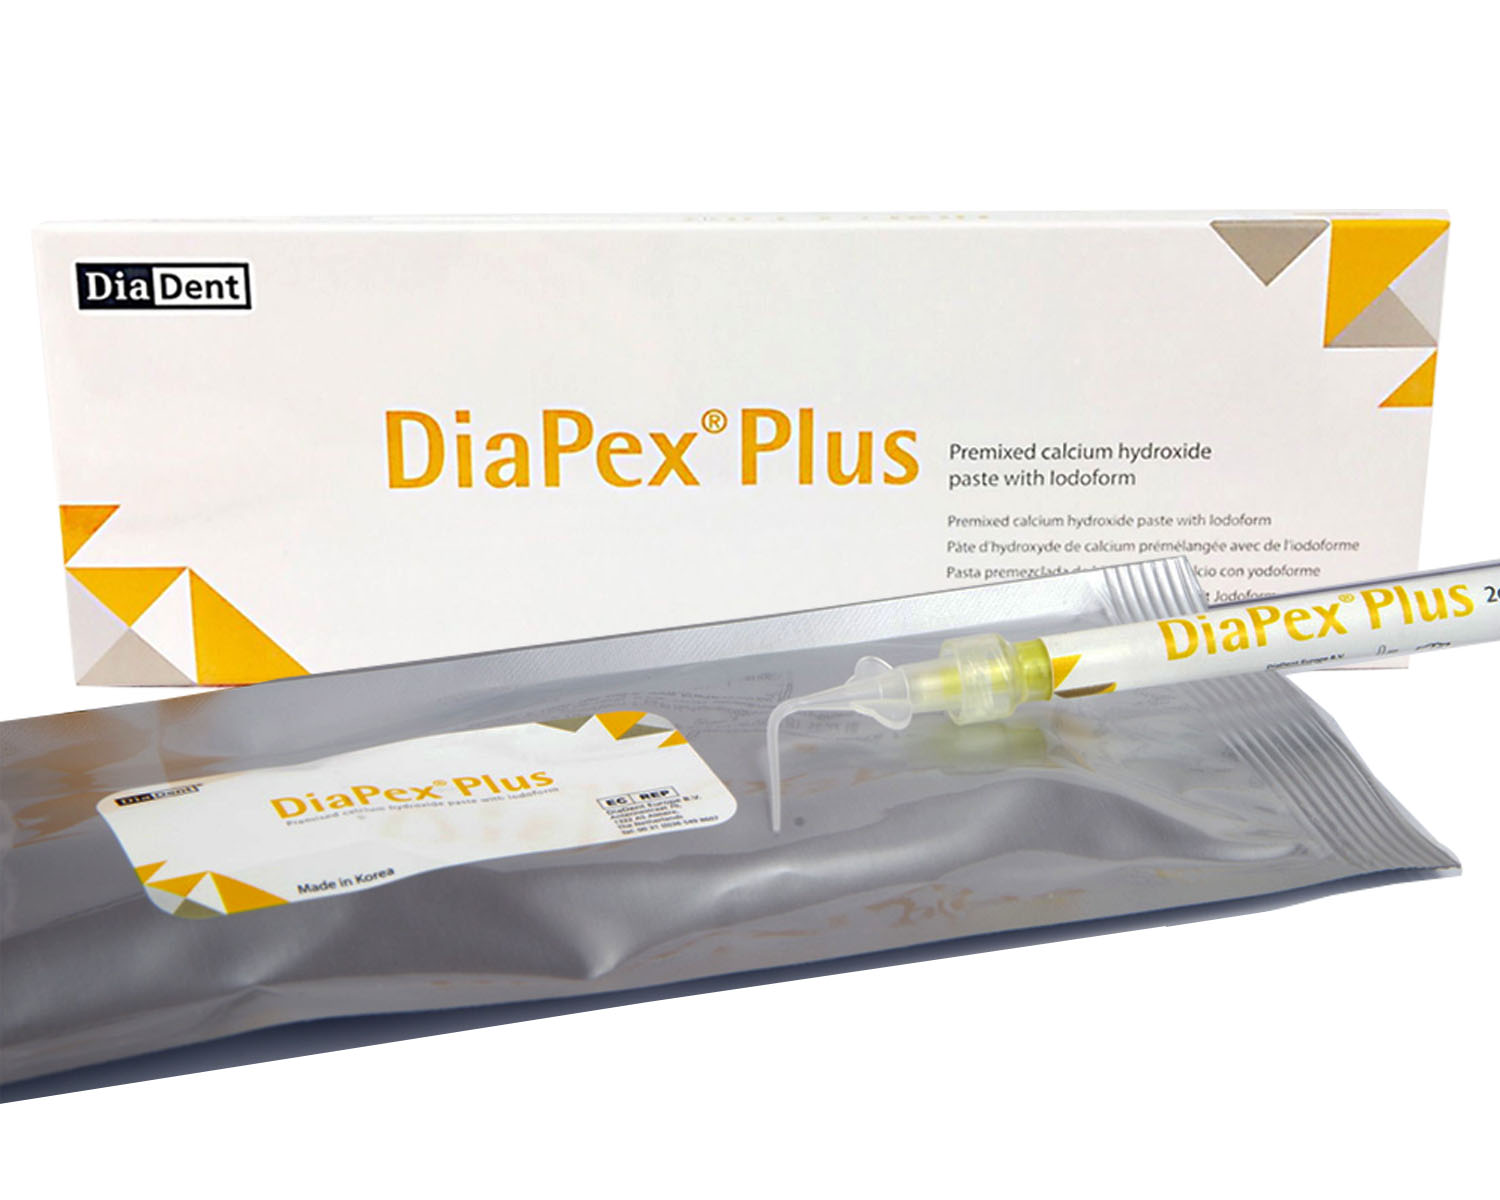

Root Canal Treatment: Diapex Plus, Diapaste, Dia-Root Bio MTA.